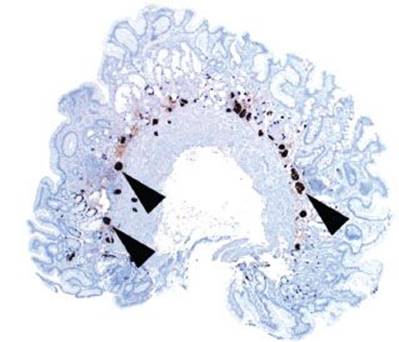

Figure 2.89 Chronic gastritis pattern, nodular ECL cell hyperplasia (chromogranin immunostain). ECL cell hyperplasia can progress to nodular form (≥5 or more ECL cells arranged in a nodule). At low magnification, the small nodular aggregates of ECL cells are evident (arrowheads). ECL cell hyperplasia, by definition, is reversible with the interruption of gastrin stimulation.

Answer: By definition, ECL cell hyperplasia refers to five or more ECL cells arranged in a back-to-back configuration, either grouped in a row (linear ECL cell hyperplasia) (Fig. 2.88) or in a cluster (nodular ECL cell hyperplasia) (Fig. 2.89). ECL cell hyperplasia is seen in 33% to 100% of patients with AMAG and is best visualized with a chromogranin immunostain.